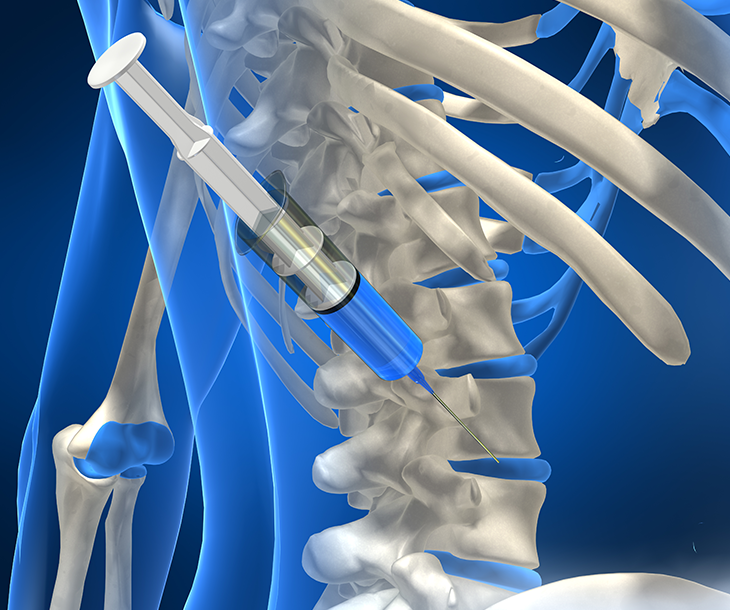

관절낭 내 주사

관절낭 내 주사는 반려동물 골관절염에 도움이 됩니다.염증억제 및 통증 완화 작용이 가능하여 수술 없이 예방과 치료가 가능합니다.